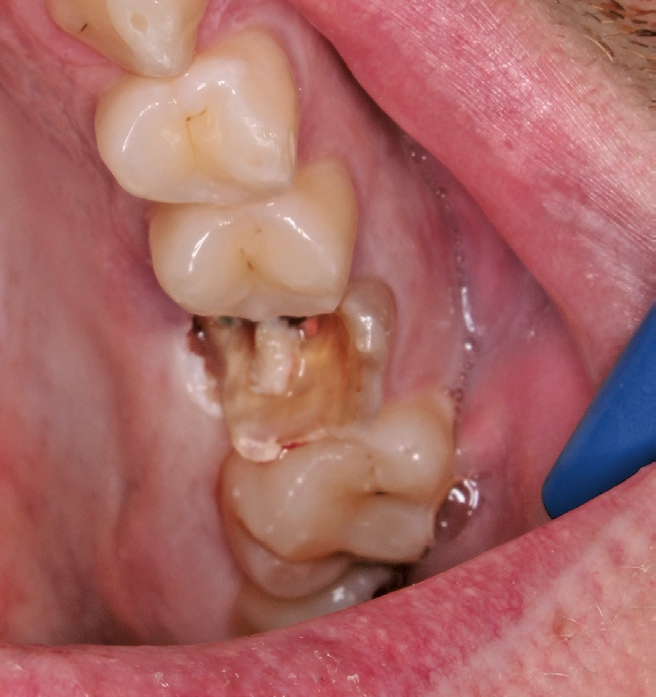

Ein 21-jähriger Patient stellte sich mit einer Perkussionsempfindlichkeit in regio 26 vor. Die klinische Untersuchung zeigte einen tiefzerstörten Zahn 26, dessen gesamte palatinale Wand tief fraktruiert war. Die Frakturgrenze verlief dabei weit unter dem palatinalen Zahnfleischrand (Abb. 1). Nach Erstellung eines Orthopantomogramms und einer radiologischen Einzelzahnbildaufnahme war eine längliche Verschattung am Apex der palatinalen Wurzel des Zahn 26 zu erkennen (Abb. 2), die den Verdacht einer überinstrumentierten Wurzelkanalaufbereitung der palatinalen Wurzel und einer Überstopfung des Füllmaterials bestätigte (Abb. 3). Nach konservierender Theapie wurde die Indikationsstellung für die Extraktion des Zahnes 26 mit einer Sofortimplantation gestellt. Der Periodontal-Screening-Index wies in allen Sextanten Grad 2 auf. Es folgte die Erstellung einer dreidimensionalen Röntgenaufnahme (Orthophos XG 3D, Dentsply Sirona, Bensheim) zur virtuellen Planung der Implantatposition. Die operative Planung erfolgte in der Planungssoftware coDiagnostiX 9.5 (dental wings, Montreal, Kanada) (Abb. 4).